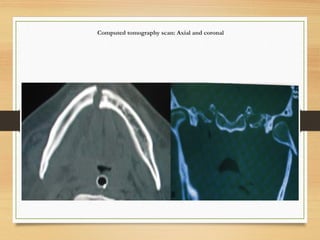

Advanced diagnostic modalities

• Computed tomography scan: when there is

intracapsular condylar fracture or complex maxillofacial

fracture

Computed tomography scan: Axial and coronal